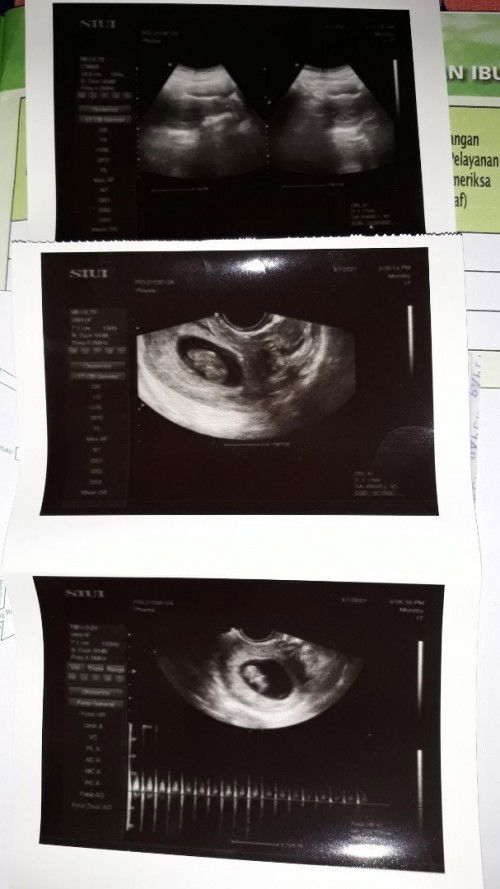

Assalamualaikum bunda² Saya mau berbagi cerita saya malam ini setelah USG, jujur pertama saya senang karena bisa tahu keadaan dedek di dalam perut, tp setelahnya saya gelisah..😞 Tadi saya USG di dokter spesialis kandungan daerah saya. Memang sebelum saya hamil haid saya sangat tidak teratur, pernah juga satu- 2 bulan tidak haid. Saat ini saya sedang hamil 12w3d (berdasarkan HPHT), dan ini pertama kalinya saya USG. Awalnya yang ada difikiran saya, janin saya sehat, dan ukurannya yaa seperti yg di TAP ini.. ternyata saya salah, bahkan tidak menyangka bahwa UK saya berdasar USG selisih jauh dr perhitungan HPHT, selisih 1 bulan, yaitu 8w4d. Dokter juga kaget saat itu, dan memastikan apa benar UK saya itu sudah 12w, lalu ditanya apakah haid nya teratur atau tidak.. Bukan hanya itu yang membuat aku kaget bund, kata dokter janinku ini ķecil bund untuk usia segitu (8w4d), aku disuruh banyak makan protein dan.hanya boleh mengkonsumsi buah alpukat. Panjang janinku 2,5 bun😥 katanya seharusnya 3,5an Yang buat saya deg2an bgt, td saya sampai di USg 2x karna USG pertama ga kelihatan bun (kaya gambar paling atas) 😭 dan yg kedua baru kelihatan dg USG lwat Vagina, agak lega juga karna ada detak jantungnya jg.. 218 kira2 normal ga ya bun untuk uk 8w4d, karna aku tadi tanya dokter, dokternya menjelaskannya membingungkan bund, selalu yg dibahas kecil, kecil, dan kecil.. jujur itu sangat membuat saya sedih bun😓 dokter td jg bilang rahimku ini agak kebelakang, dan aku tanya apakah bahaya, dokter mlah lgsung nyeplos ya bisa susah hamil😭 lah semakin mak deg bund saya😅 trs dokter bilang lagi, tp ini kan sudah hamil berarti aman..lega lagi saya😄 Akhirnya dokter bilang lihat perkembangan bulan depan bagaimana, krn itu akan berpengaruh jg pada hpl nya.. setelah saya keluar dr ruangan, saya bilang sm mbk ip saya, dia cemas juga seperti saya, dia menyarankan saya untuk coba priksa lagi ke dokter lainnya, biar lebih pasti. Suami ngikut aja, dan akhirnya mau coba periksa lagi minggu depan, krn kami fikir dicoba dulu perbanyak protein dan alpukatnya, ada perubahan engga sampai minggu depan... Saya pulang dr USG dengan rasa gelisah bun, sedih bgt rasanya, berusaha relax tp kok kepikiran. Mungkin bunda ada yg punya pengalaman sama atau hampir seperti saya, boleh dishare bund, bantu saya melakukan yg terbaik untuk janin saya bund😓😓 Mohon maaf sebelumnya kalau kepanjangan, Terimakasih untuk bunda² yg sudah menyempatkan membaca dan memberi masukan🙂 Wassalamualaikum #seriusnanya #bantusharing #jangandibully